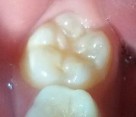

Bệnh nhân: Trần Nguyệt H. 7 tuổi, Răng 46, mã BA 11907/17

Sau sáu tháng. ICDAS: 1; Di: 15 | Sau chín tháng. ICDAS: 0; Di: 13 | Sau 18 tháng. ICDAS 0; Di:7 |